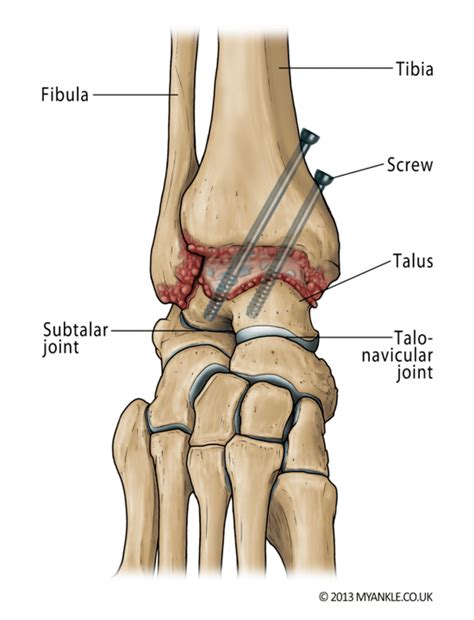

• Incision: The surgeon makes an incision in the ankle to access the joint.

• Bone Preparation: The cartilage and any damaged bone are removed from the joint surfaces to prepare them for fusion.

• Bone Grafting: In some cases, bone grafts may be used to promote healing and fusion. These grafts can be taken from the patient's own body or from a donor.

• Fixation: The bones are aligned and held in place using screws, plates, or rods. These fixation devices provide stability while the bones heal and fuse together.